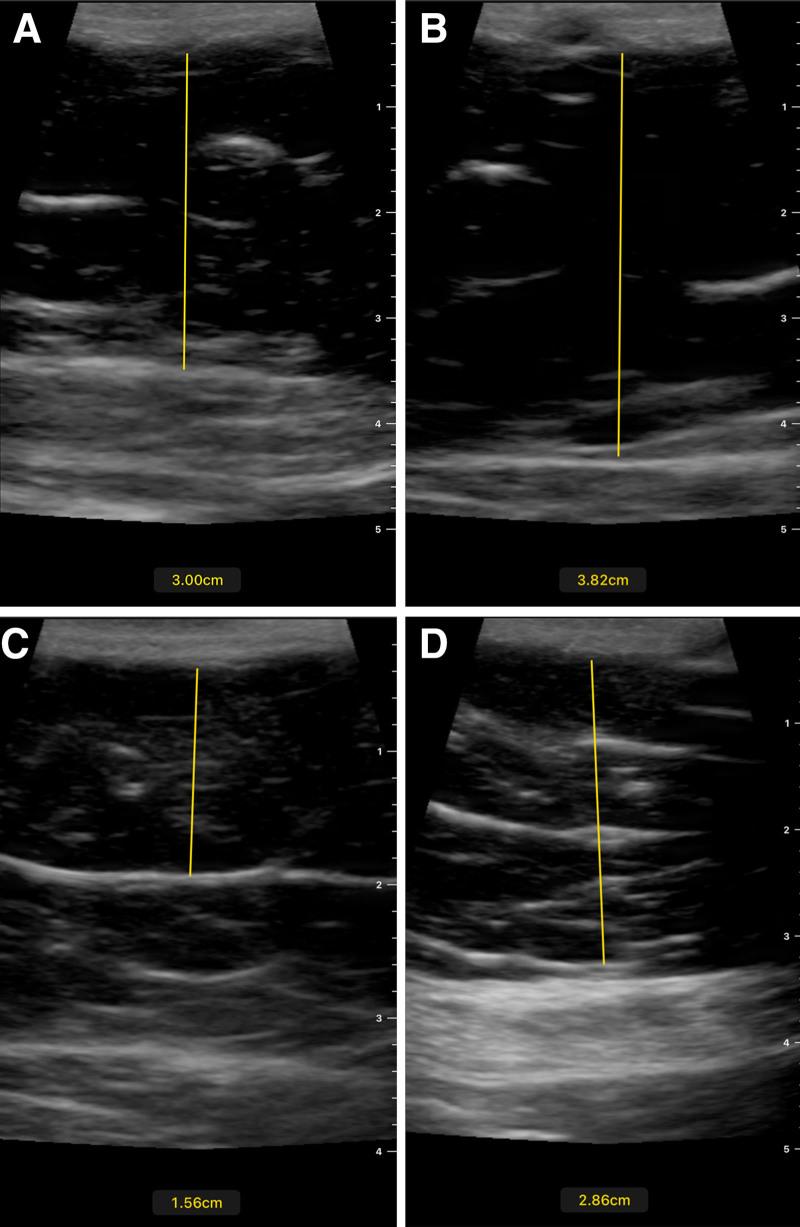

Noninvasive body contouring has seen a precipitous rise in popularity since its advent in the early 2000s. With this rise in popularity, there has been an expansion in the types and number of noninvasive devices for muscle hypertrophy and fat lipolysis. The Transform radiofrequency and electrical muscle stimulation device is a newly introduced device for noninvasive abdominal body contouring. The present study is a prospective clinical trial evaluating the efficacy of the Transform device on abdominal circumference. Fifteen patients were enrolled and received three treatment sessions with the Transform device. On average, patients saw changes in abdominal circumference (-0.43 cm, = 0.48), caliper pinch thickness (-6.07 mm, = 0.0036), and ultrasound fat thickness (-5.40 mm, < 0.001) at 3 months posttreatment with minimal discomfort and high patient satisfaction. Ultimately, this study demonstrates that the Transform device is a safe and effective noninvasive option for fat lipolysis and muscular hypertrophy.

自21世纪初问世以来,非侵入性身体塑形的受欢迎程度急剧上升。随着其受欢迎程度的提高,用于肌肉肥大和脂肪分解的非侵入性设备的类型和数量有所增加。Transform射频和电肌肉刺激设备是一种新推出的用于非侵入性腹部塑形的设备。本研究是一项前瞻性临床试验,评估Transform设备对腹围的疗效。招募了15名患者,他们接受了三次使用Transform设备的治疗。平均而言,患者在治疗后3个月时腹围(-0.43厘米,标准差=0.48)、卡尺捏起厚度(-6.07毫米,P=0.0036)和超声脂肪厚度(-5.40毫米,P<0.001)有变化,不适最小且患者满意度高。最终,本研究表明Transform设备是脂肪分解和肌肉肥大的一种安全有效的非侵入性选择。